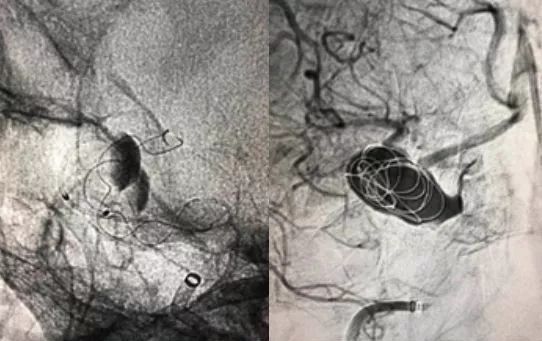

3、Tubridge释放

Tubridge血管重建装置4.0mm*35mm经T-track到位,锚定Tubridge头端,缓慢推送、释放Tubridge,“推支架、撤微导管张力”全程缓慢减张释放,支架尾端接近释放状态约2mm时,撤微导管T-track张力,支架弹开,近端贴壁。造影显示支架展开贴壁良好,动脉瘤内血流明显滞留。

5、填圈

用预留的微导管Ethelon10完成瘤内2枚弹簧圈填塞,因为AN位于硬膜环以外,床突段,瘤颈不算太大,仅“稀疏填塞”。术后即刻效果显著,瘤内血栓形成,分支血管通畅。